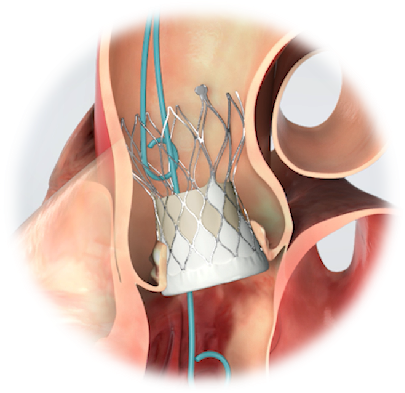

图片3:TAVR示意图

考虑到实施常规开胸体外循环手术难度高、风险大,依老唐目前的状况,是不可能完成的。心脏大血管外科主任潘禹辰带领团队联合心血管内科、麻醉科、手术室、介入室、肾内科、营养科、康复科等进行了多学科会诊,并将手术风险充分告知患者家属,在结合患者实际病情综合评估、征得家属充分理解之后,救治团队决定采用“微创不开胸换瓣手术”,即经导管主动脉瓣置换术(TAVR)。

对严重主动脉瓣病变患者,常规外科体外循环直视下主动脉瓣置换术(SAVR)曾经是唯一可以延长生命的治疗手段,但老年患者常因高龄、体质弱、病变重或合并其它疾病而不能手术。对于存在高危或有外科手术禁忌的患者,现在,经导管主动脉瓣置换术(TAVR)则可以作为一种有效的治疗手段,具有创伤小、恢复快、风险低等优点。既往做TAVR手术的绝大多数患者都是主动脉瓣严重钙化狭窄,因为有钙化的锚定区易于瓣膜固定,而主动脉瓣返流的患者,瓣环及瓣上结构一般都较大,锚定区少,因此,单纯主动脉瓣严重返流的患者实施TAVR手术难度非常大,某些患者因缺乏锚定区而无法实施微创手术。